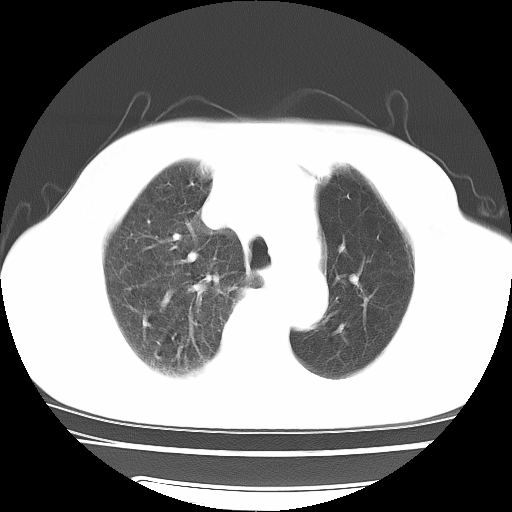

男,71岁,咳嗽,气喘10年,再发并咯血.胸片见气胸

考虑  左肺中心型肺癌伴阻塞性肺炎,肺不张,纵膈淋巴结肿大。慢支炎,肺气肿,左侧气胸肺压缩5%

1)考虑左肺中心型肺癌伴阻塞性肺炎、左肺下叶肺不张、左侧肺气肿,纵膈淋巴结转移。2)左侧气胸(肺组织压缩约5%)。

左肺中心型肺癌伴阻塞性肺不张、肺气肿 。

1)考虑左肺中心型肺癌伴阻塞性肺炎、左肺下叶肺不张、左侧肺气肿,纵膈淋巴结转移。2)左侧气胸。